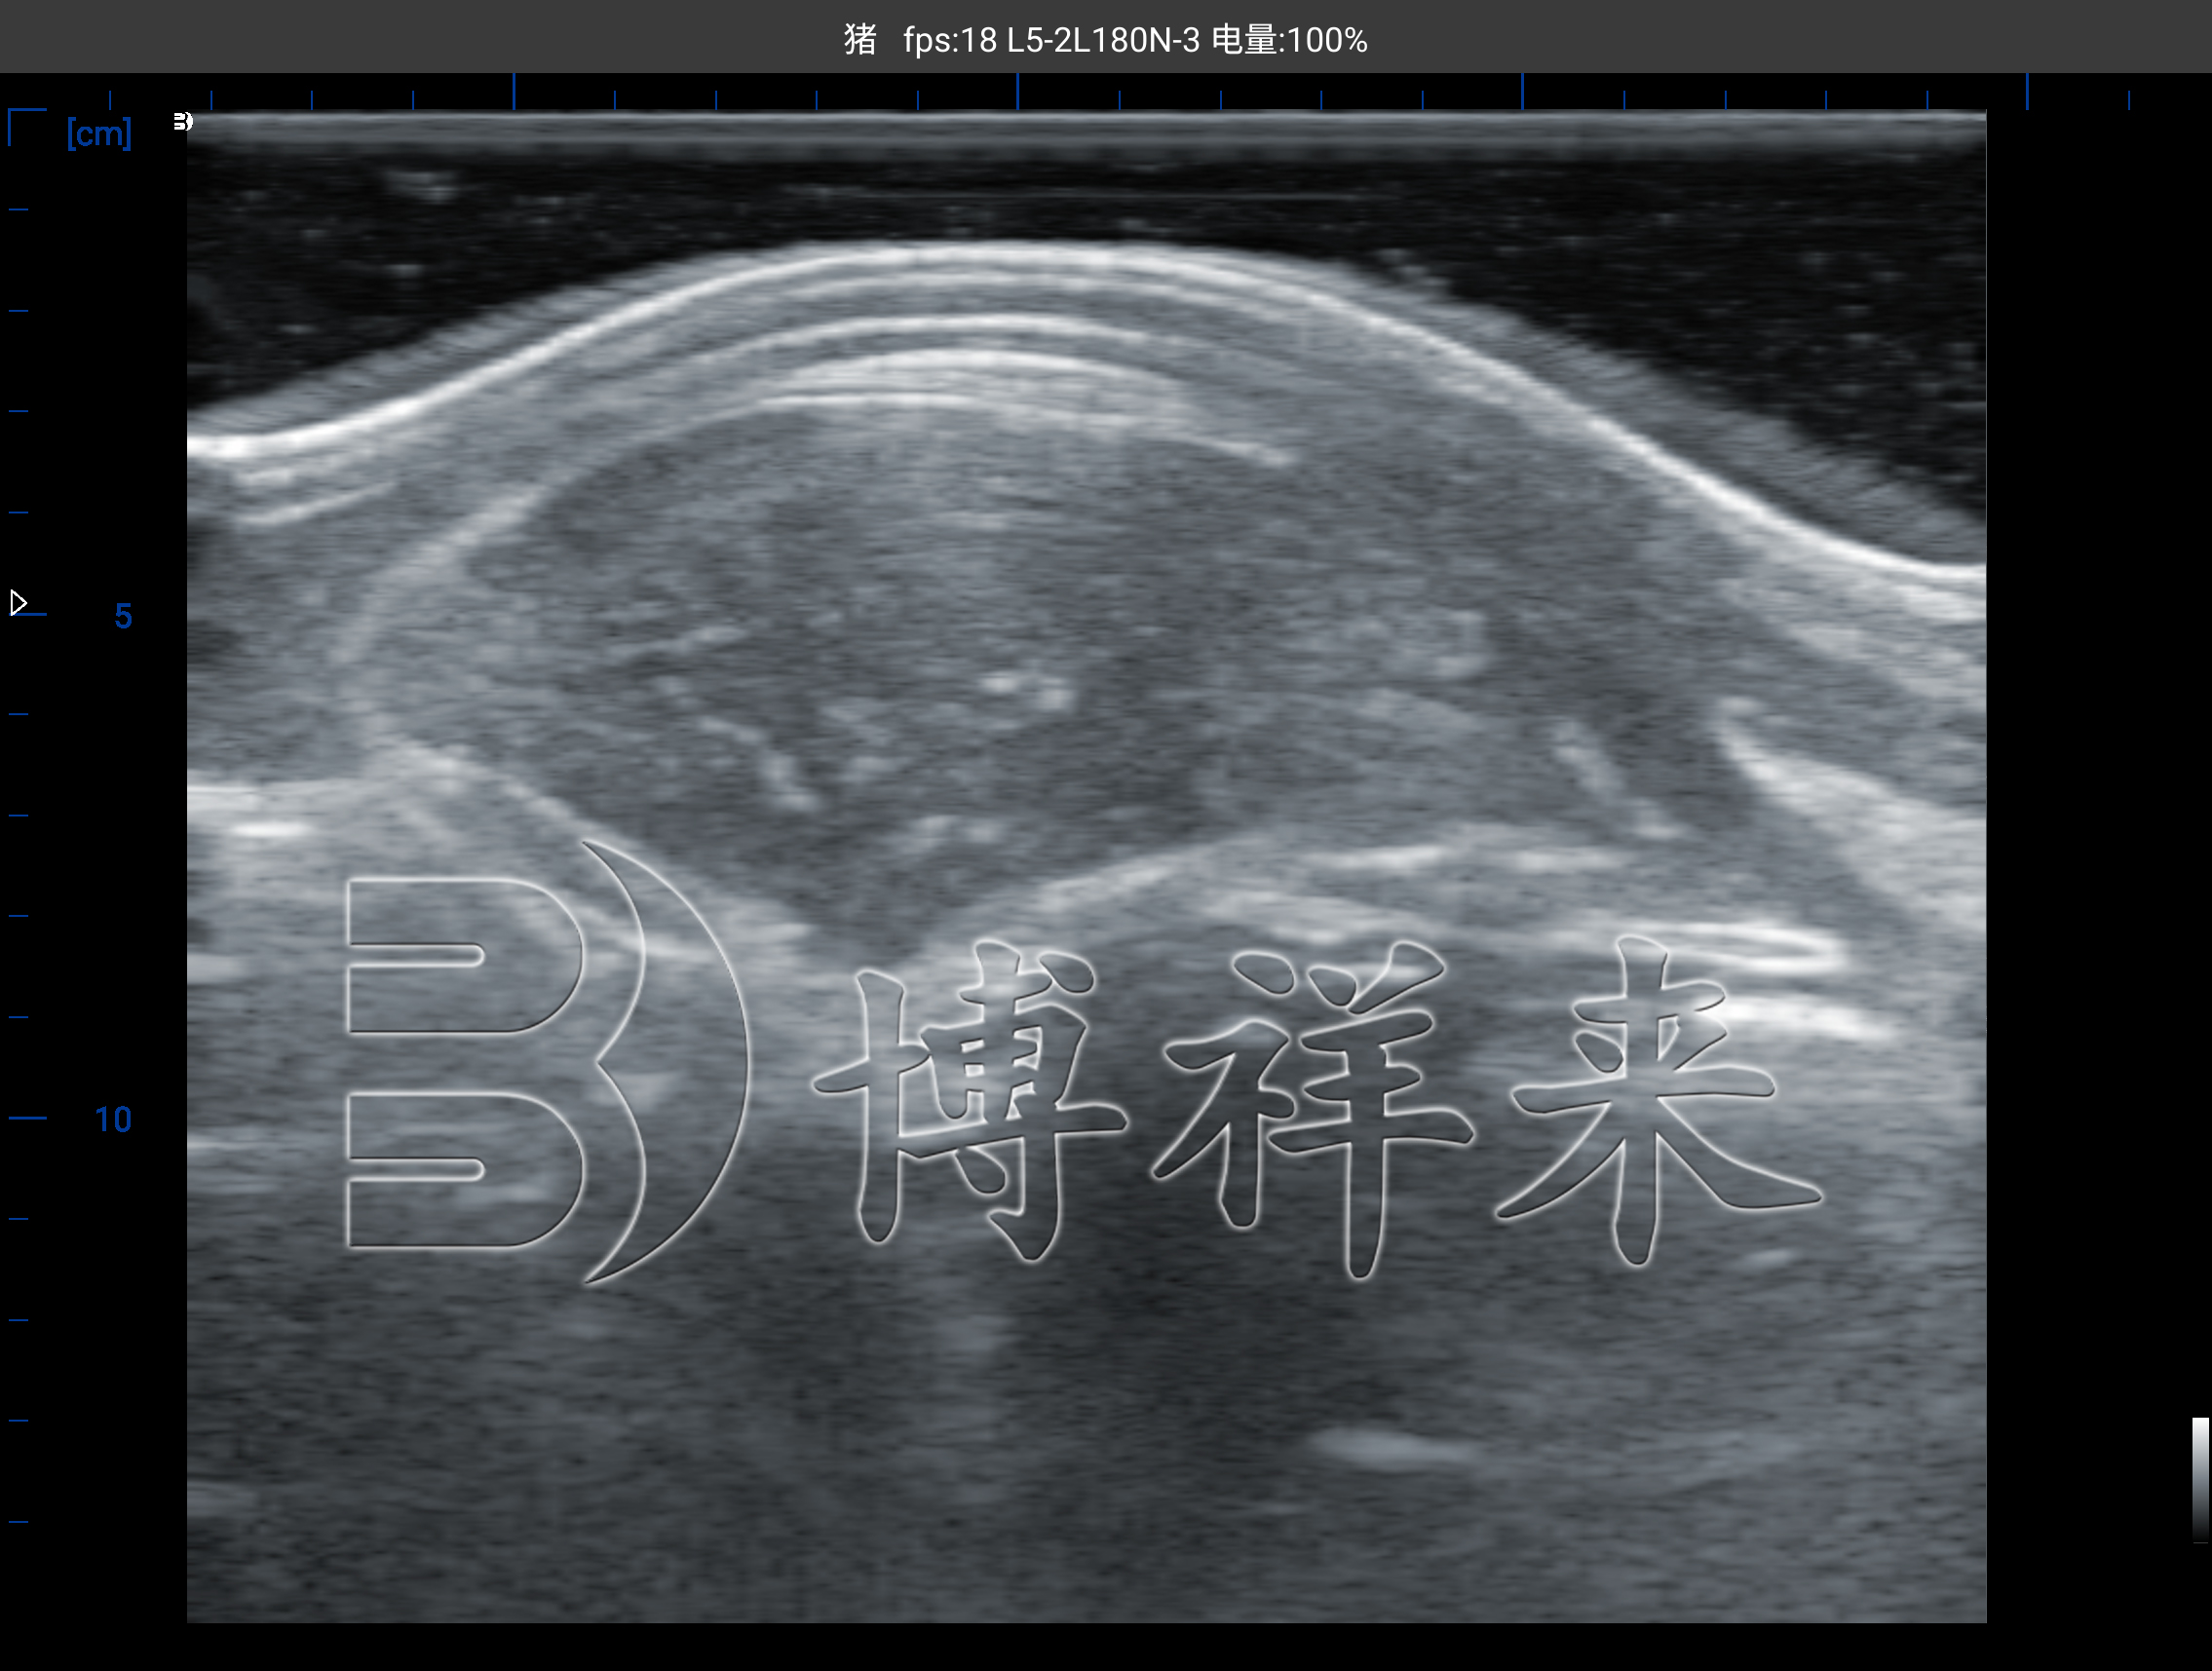

在传统育种管理中,选种往往依赖人工观察和体型估计,这种方式主观性强,误差较大。而智能背膘仪通过B超图像直接呈现背膘与眼肌结构,让育种决策从“凭感觉”变为“看数据”。

通过对猪体第10肋处进行检测,仪器可清晰显示:

背膘层的厚度与均匀性;

眼肌面积与形态;

肌肉与脂肪的比例结构。

这些数据直接反映猪的遗传潜力和育种方向,是精准选育高品质种猪的重要依据。